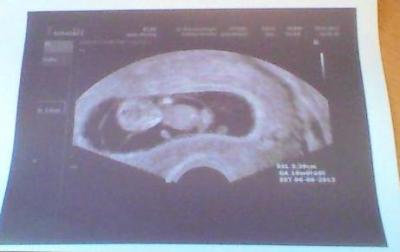

Hallo Zusammen, hoffe es geht euch alle gut . Mir gehts echt super, habe grad meinen kleinen Zwerg gesehen. Wir sind heute bei 10+3 und das Kleine ist 3,4 cm (SSL) groß. Außerdem hat es sich beim Ultraschall ganz toll bewegt. Die Ärmchen wanderten immer wieder Richtung Mund, die Beine strampelten und es gab als "Zugabe" sogar eine ganze Drehung. Selbst die Frauenärztin war total begeistert. Außerdem war ich der Meinung, dass es eindeutig zu erkennen ist, dass es ein Junge wird (wircklich sehr eindeutig), aber die FA meinte, dass sie es zwar auch sieht, es aber noch viel viel zu früh es um es sagen zu können. Also heißt es abwarten bis zum nächsten Ultraschall.

Es ist echt ein großes Wunder, wenn man sieht was aus unseren Pünktchen geworden ist, auf deinem Bild kann man schon richtig sehen, daß es tatsächlich mal ein Baby wird. Ich bin mal gespannt ob sich deine Vermutung bestätigt. LG